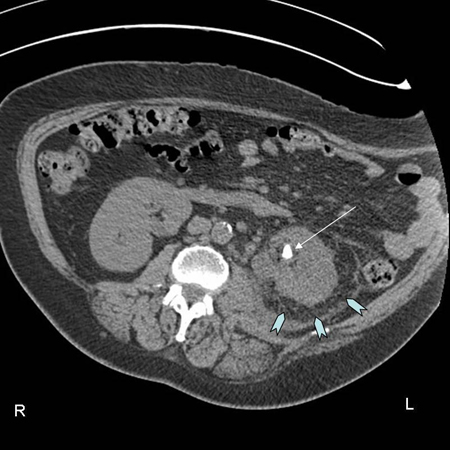

CT scan showing left renal stone (white arrow) with perinephric stranding around the left kidney (blue chevrons) and pyelonephritis

From the personal collection of Dr Kasra Saeb-Parsy